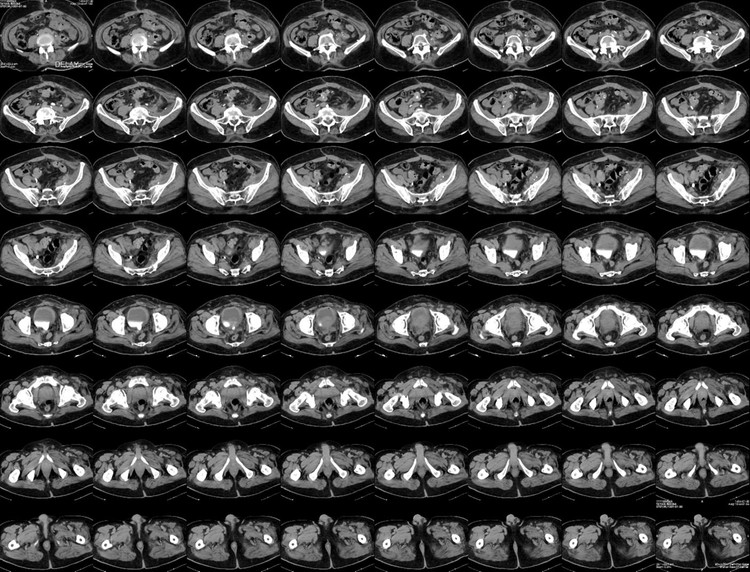

بی شک بلو فیلم های رادیولوژی با شاخص 1760 dpi به بالا جایگزین اقتصادی مناسب فیلم های رادیولوژی خواهند بود .

باخرید یک پرینتر زیر بیست میلیون تومانی مرکز خود را از وابستگی به خرید فیلم های رادیولوژی با محدودیت رها کنید .

بدون شک شما میتوانید بدون پرداخت هزینه های سنگین و با پرداخت هزینه ای حدود نصف سایر فیلم های پزشکی مرکز تصویربرداری خود ( بخش های سی تی اسکن و ام ار ای ) را به خروجی کلیشه های تصویر برداری مجهز کنید .